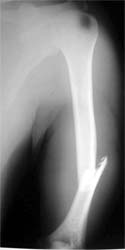

肱骨干骨折 采用闭合穿钉法,带锁髓内钉内固定,10个月后骨折愈合